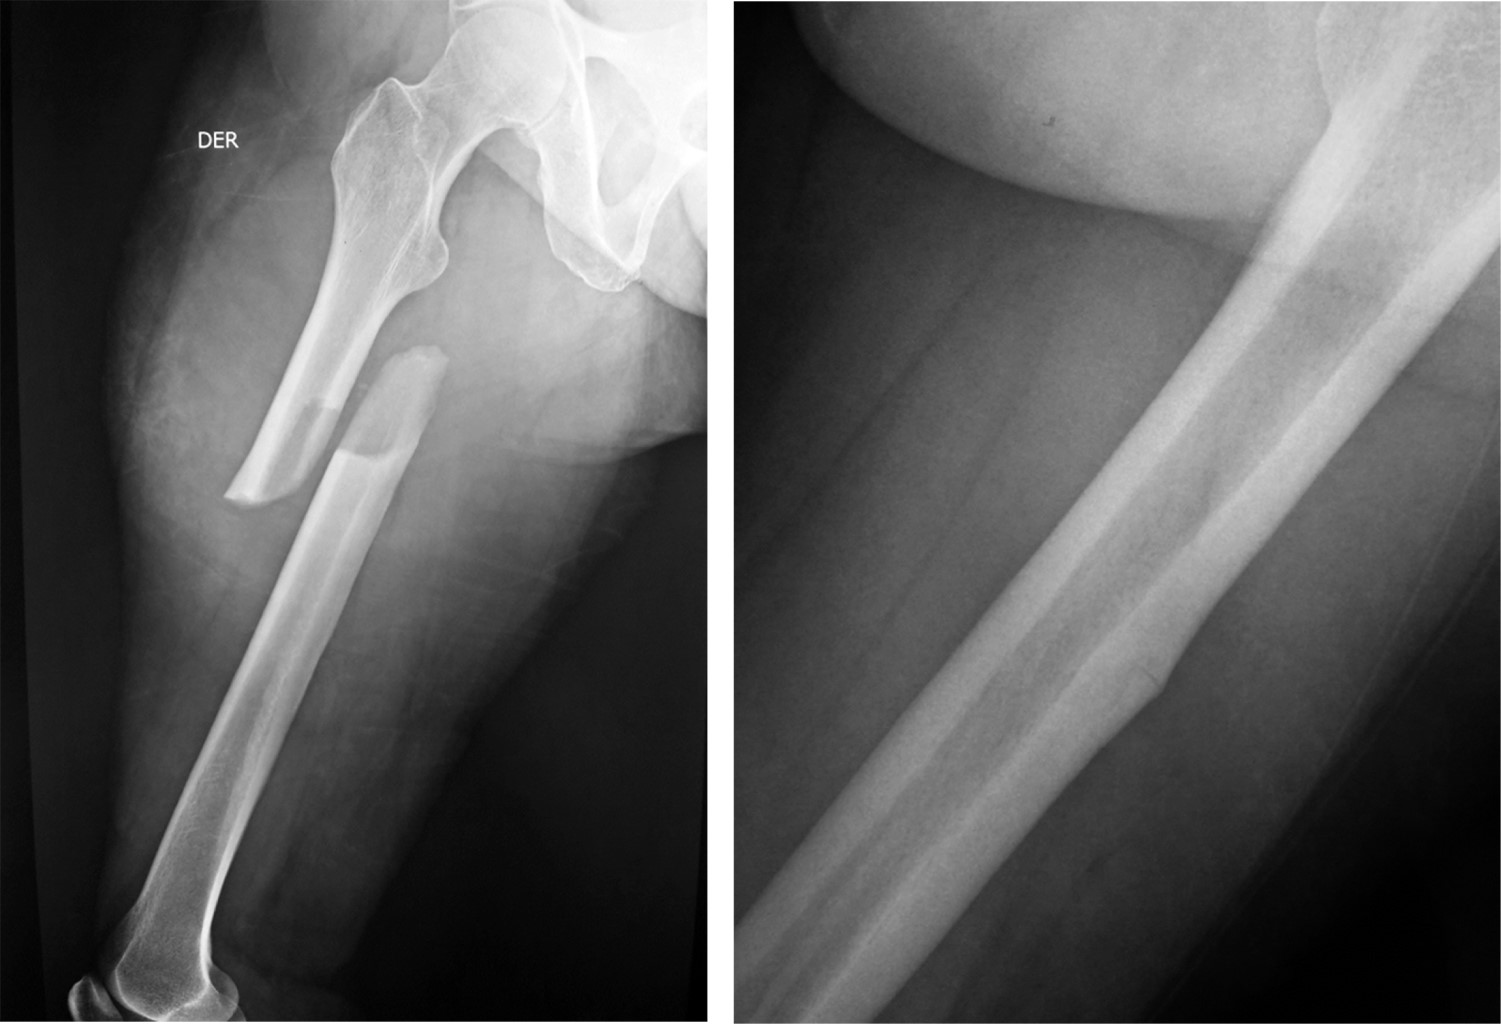

Dentro de su utilidad clínica destaca el efecto positivo que tiene para el manejo de la osteoporosis, siendo éste su principal motivo de prescripción.6,7 Los reportes e investigaciones realizadas posterior a la comercialización de los bifosfonatos han asociado la administración de estos fármacos con efectos adversos previamente desconocidos, dentro de los que se encuentran las fracturas de fémur de trazo atípico (Figura 1).8 Para identificar este tipo de fracturas, la American Society for Bone and Mineral Research ha propuesto una definición de caso basada en criterios que se detallan en la Tabla 1.9,10

Figura 1